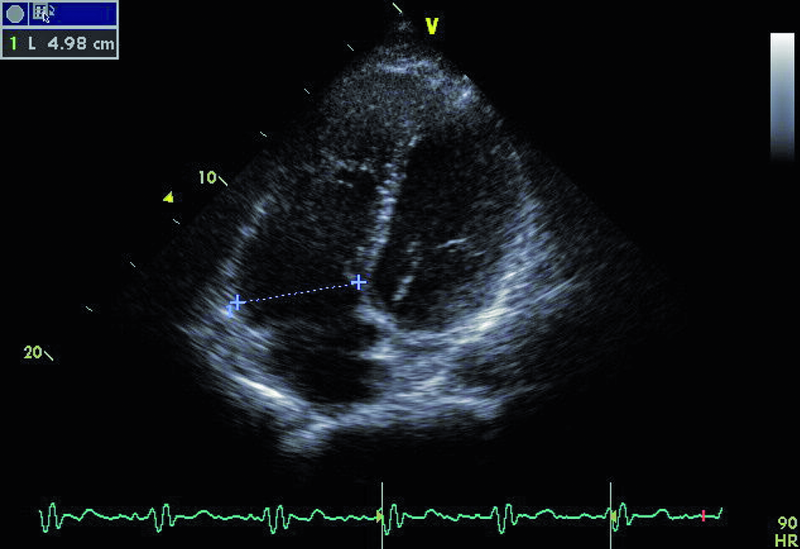

Droga odpływu prawej komory u opisanego chorego jest szeroka i z pewnością nie stanowi zapory dla przepływającej krwi (ryc. 1). Częstym powikłaniem całkowitej korekcji tetralogii Fallota, zwłaszcza z wykorzystaniem łaty przezpierścieniowej, jest duża niedomykalność zastawki płucnej, którą stwierdzono również u opisanego chorego. Strumień niedomykalności w badaniu kolorowego doplera jest szeroki i pokrywa prawie cały przekrój drogi odpływu (ryc. 2). Niedomykalność zastawki płucnej trudno ocenić ilościowo za pomocą techniki ultradźwiękowej. Złotym standardem diagnostyki jest rezonans magnetyczny, który pozwala określić tzw. frakcję niedomykalności. Spośród parametrów echokardiograficznych najbardziej zbliżonym i dość wiarygodnie odzwierciedlającym stopień niedomykalności zastawki płucnej jest czas połowicznego zmniejszenia gradientu ciśnień między pniem płucnym a prawą komorą (pressure half time, PHT). PHT krótszy niż 100 ms świadczy o istotnej niedomykalności zastawki płucnej (ryc. 3). Innym, nieanalizowanym w ilustracjach parametrem może być tzw. indeks niedomykalności, czyli iloraz czasu trwania fali zwrotnej płucnej do czasu trwania rozkurczu. Niedomykalność zastawki płucnej, nawet tak duża, jak w opisanym wypadku, nie musi istotnie ograniczać tolerancji wysiłku. W takiej sytuacji obowiązuje jednak precyzyjna ocena wielkości i funkcji prawej komory serca. Stopień powiększenia prawej komory u tego chorego jest umiarkowany (ryc. 4), a funkcja kurczliwa mięśnia mierzona za pomocą prędkości skurczowej ruchu bocznej części pierścienia trójdzielnego (S’) jest prawidłowa (ryc. 5). Dodatkowym parametrem łatwym do uzyskania niezwykle czułym w określaniu niedomogi prawej komory jest pole prawego przedsionka. Niewielkie przekroczenie górnej granicy normy, czyli 18 cm2, rejestrowane w tym przypadku (ryc. 6) potwierdza słuszność wyboru strategii zachowawczej. Chory może być nadal obserwowany, chyba że warunki anatomiczne drogi odpływu prawej komory pozwalają na przezcewnikową implantację zastawki Melody lub Edwards-Sapien. Określenie możliwości przeprowadzenia tego rodzaju interwencji ponownie wymaga jednak odniesienia się do wyników rezonansu magnetycznego lub wykonania cewnikowania serca.